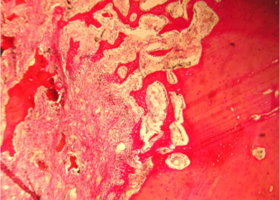

В норме кость нижней челюсти кролика имеет губчатое строение и представлена как компактным пластинчатым, так и губчатым балочным компонентами.

Пластинчатый компонент располагается по периферии на поверхности кости и представлен кортикальной пластиной, имеющей остеонный тип строения.

Губчатый компонент, имеющий трабекулярно-балочное строение, расположен внутри под кортикальной пластиной и представлен балками губчатой костной ткани, пространство между которыми заполнено миелоидной тканью, содержащей клетки красного костного мозга, единичными жировыми клетками и сосудами микроциркуляторного русла — капиллярами (рис. 1).

Рис. 1. Строение нижней челюсти кролика в норме

Губчатый компонент, имеющий трабекулярно-балочное строение, расположен внутри под кортикальной пластиной и представлен балками губчатой костной ткани, пространства между которыми заполнены миелоидной тканью, содержащей клетки красного костного мозга, единичными жировыми клетками и сосудами микроциркуляторного русла – капиллярами (рис. 1).

Рис. 1. Строение нижней челюсти кролика в норме. Черными стрелками указан компактный компонент, синими – губчатый.

Между балками губчатого вещества видна миелоидная ткань, клетки жировой ткани и капилляры (указаны зелеными стрелками).

Окраска – пикрофуксин по ван Гизон, х100.